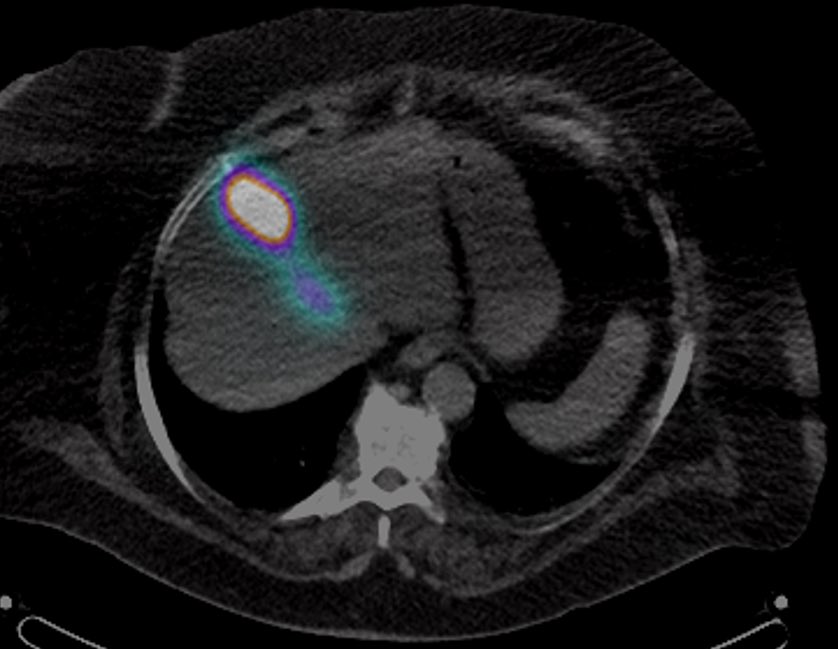

should be an AWESOME outcome #irad

Patient with seg4 HCC and celiac axis atherosclerotic occlusion (and aortioiliac disease). Difficult navigation via SMA collateral to GDA and finally seg4 branch of LHA #Y90. Hoping for a great outcome @MoffittNews @NaineshParikhMD Intra-op CTA @SiemensUSA Maestro @MeritMedical